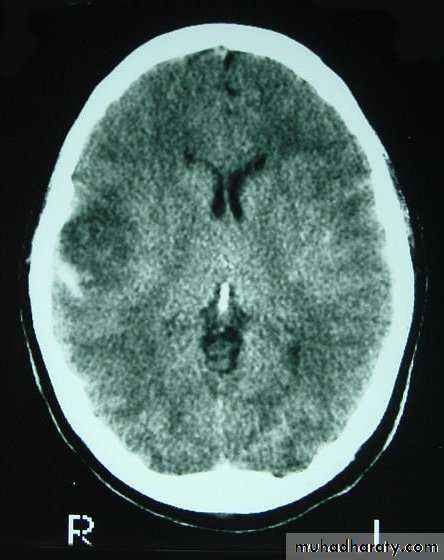

c. Intracerebral Haematoma

This is the least common of traumatic haematoma.

They are due to areas of traumatic contusion coalescing into a contusional haematoma.

Disrupted cerebral tissue release thromboplastins that potentiate haemorrhage.

CT scan: appear as hyperdence lesions with associated mass effect and midline shift.

Large intracerebral haematomas should be evacuated unless the patient’s neurological state is improving.

Small inracerebral haematomas may not require removal, but be aware that they can expand.